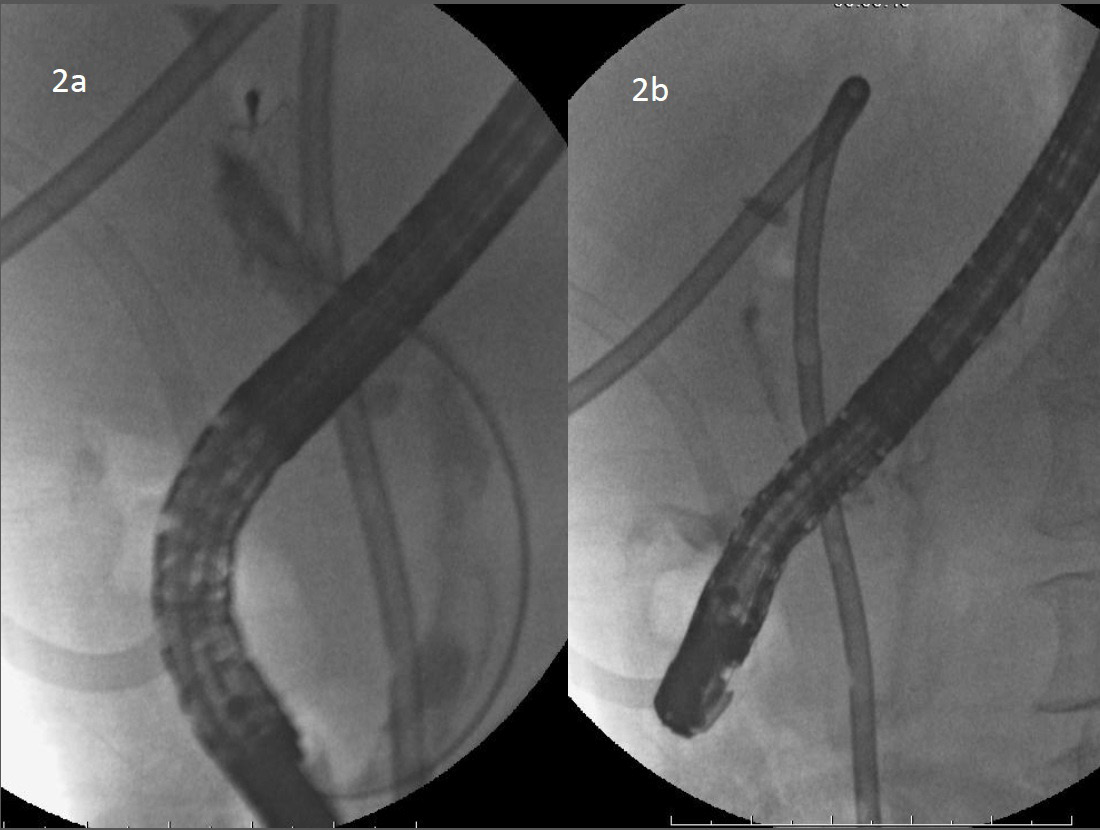

Figure 2: Luoroscopy image showed mucin related poor biliary image to figure the biliary tract.

figure 2